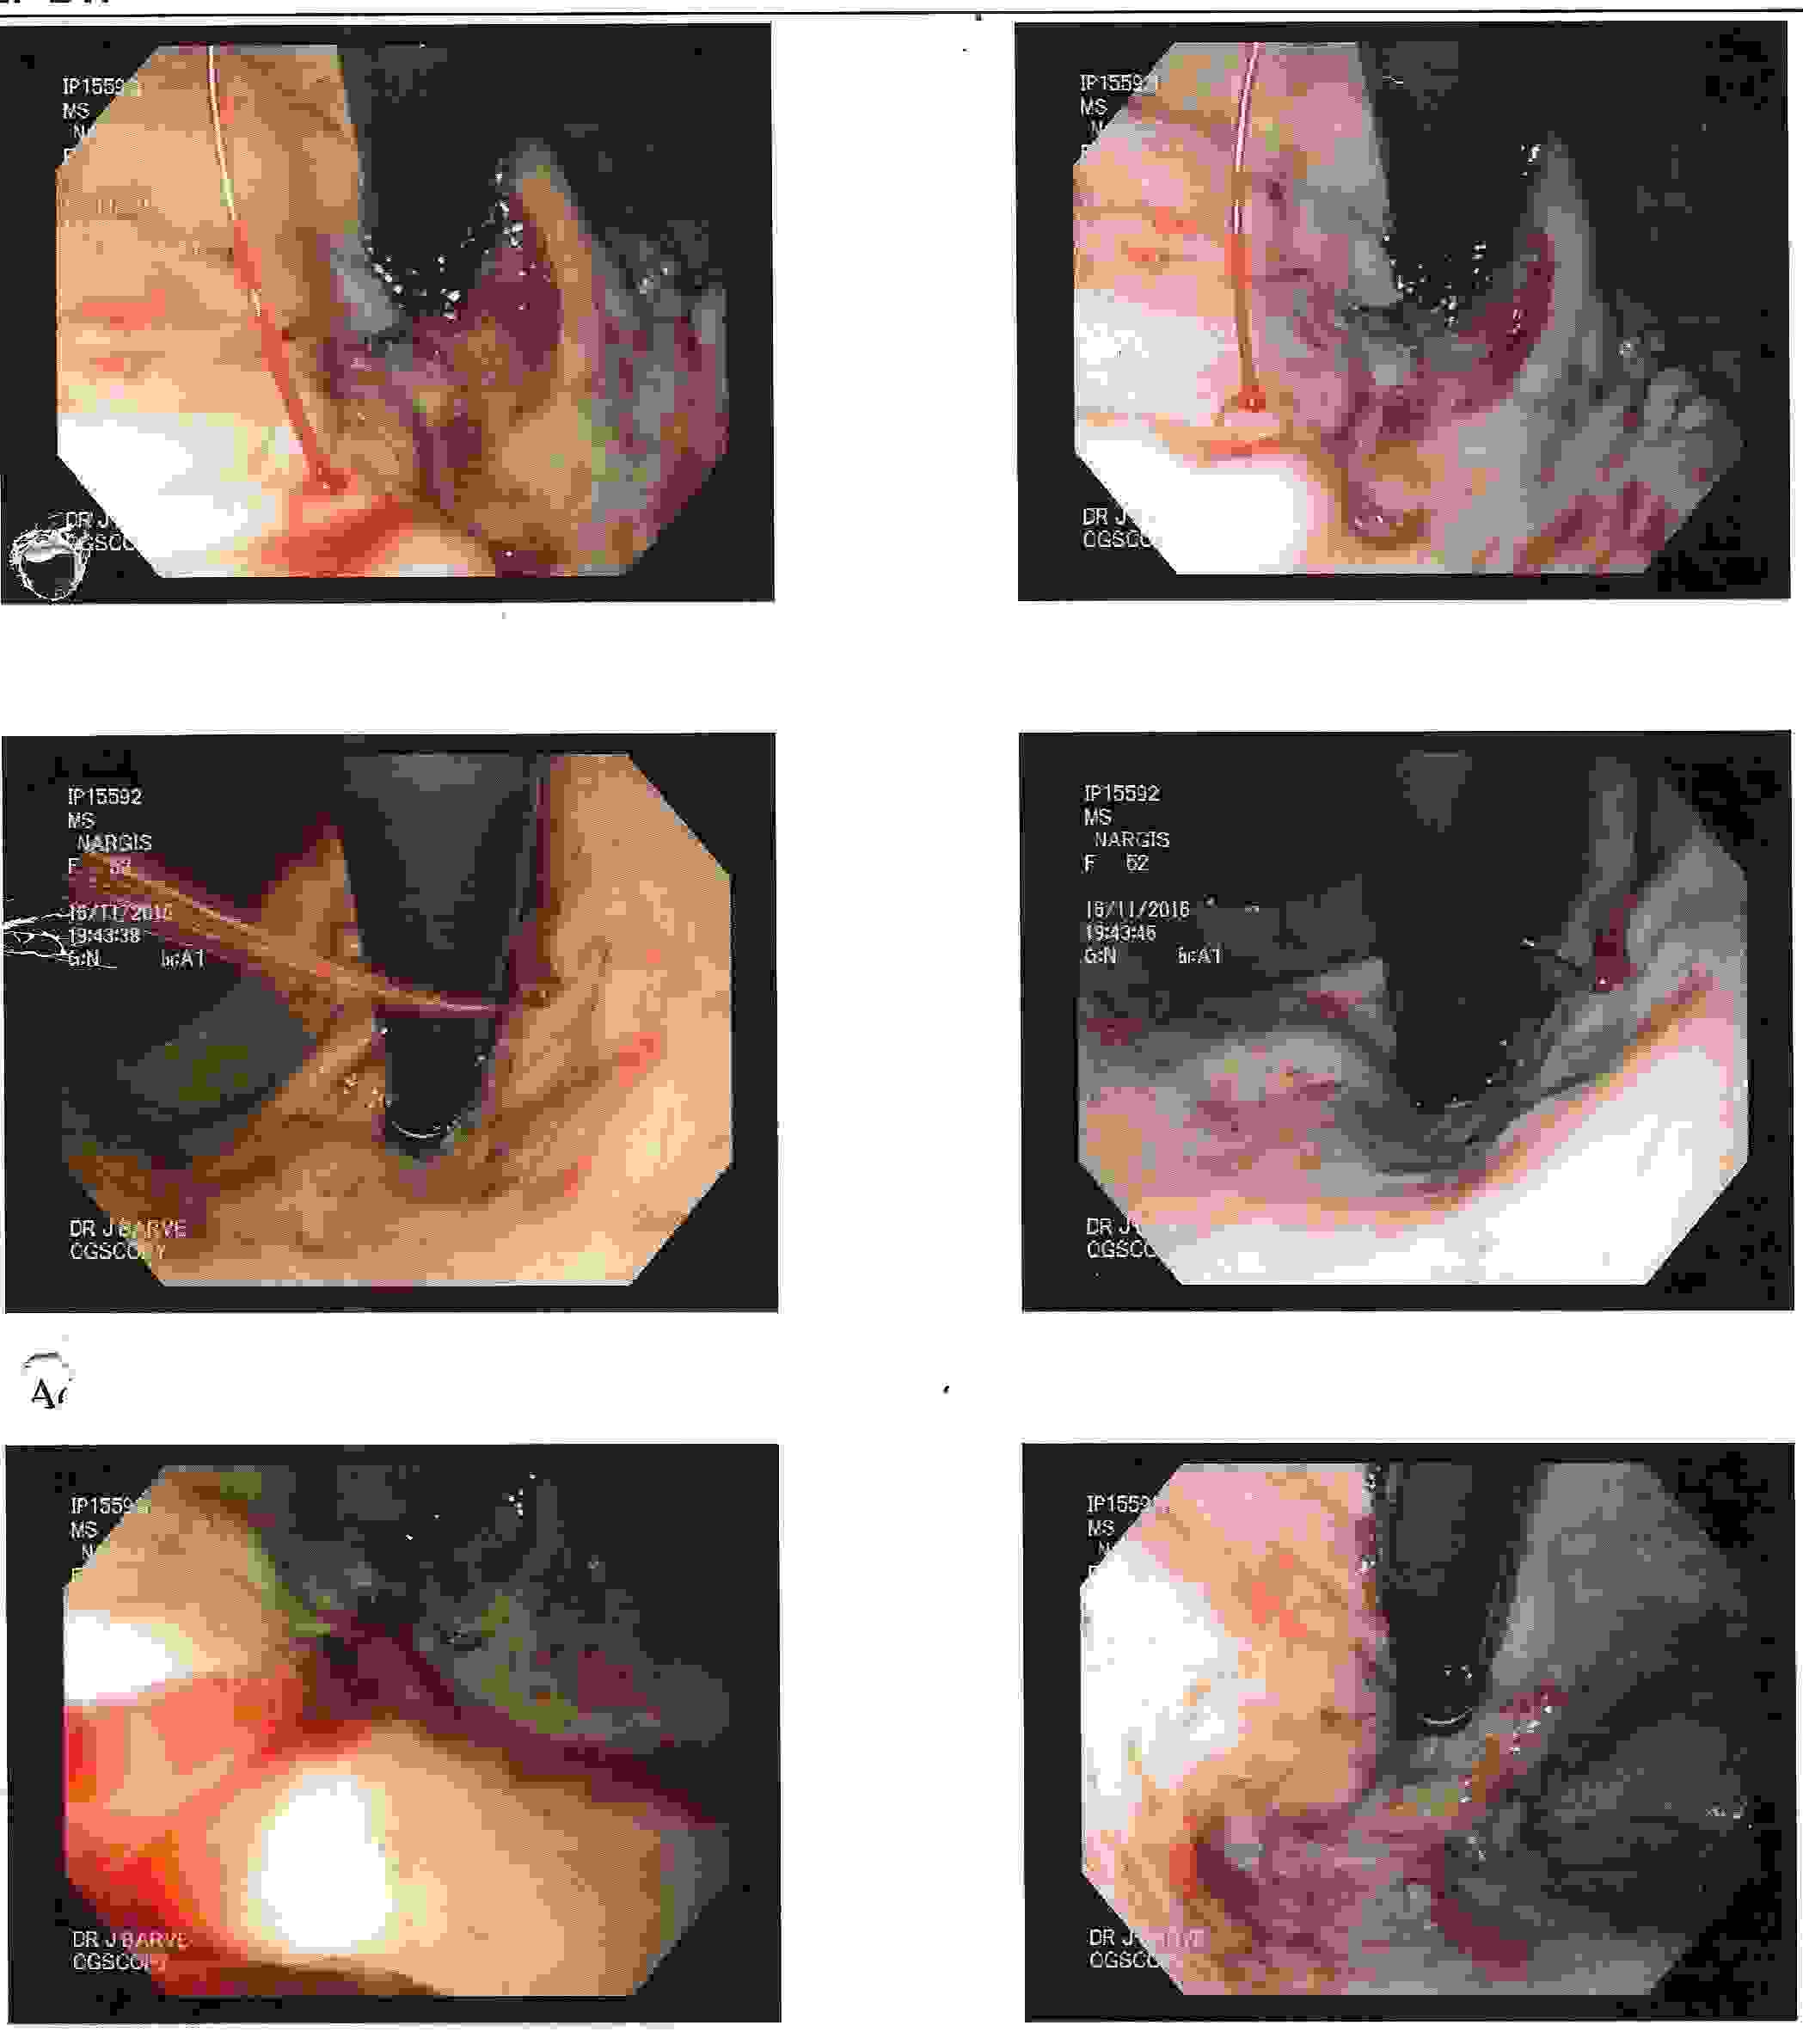

GALL BLADDER STONES TREATMENT

Endoscopic Retrograde Cholangio Pancreatography is an advanced endoscopic procedure related to

diseases of pancreas and biliary tree. Common indication for ERCP is jaundice due to obstruction

of biliary tube, which drains the bile from the liver into the intestine.

Obstruction can be due to a gallstone, which has slipped into bile tube and has blocked the bile tube.

These Stones can be removed by ERCP, without any surgery being involved.

Common Biles Duct Stones

Common Biles Duct Stones

Cancer of the Bile Tube in Duodenum

Impacted Stone in Common Bile Duct